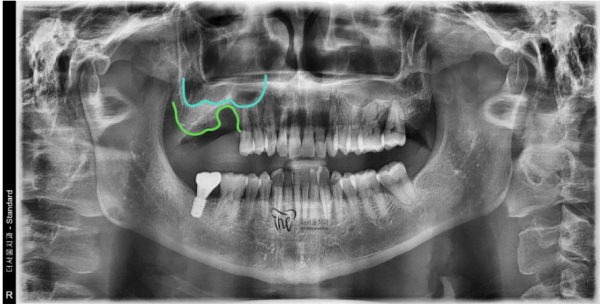

이 환자분은 충치가 심하여서 발치를 한 케이스인데요.

뿌리끝 염증으로 인해 발치를 하게되었고, 남아있는 뼈가 많이 얇아져 있었습니다.

위의 푸른색 선이 바로 상악동의 경계면이고, 밑의 녹색 선이 위턱의 뼈 입니다.

그 두께가 매우 얇은것을 알 수 있습니다.

This patient had his tooth removed due to severe tooth decay.

The root tip inflammation caused the extraction, and the remaining bones were very thin.

The upper blue line is the boundary of the upper jaw, and the lower green line is the bone of the upper jaw.

You can see that the thickness is very thin.